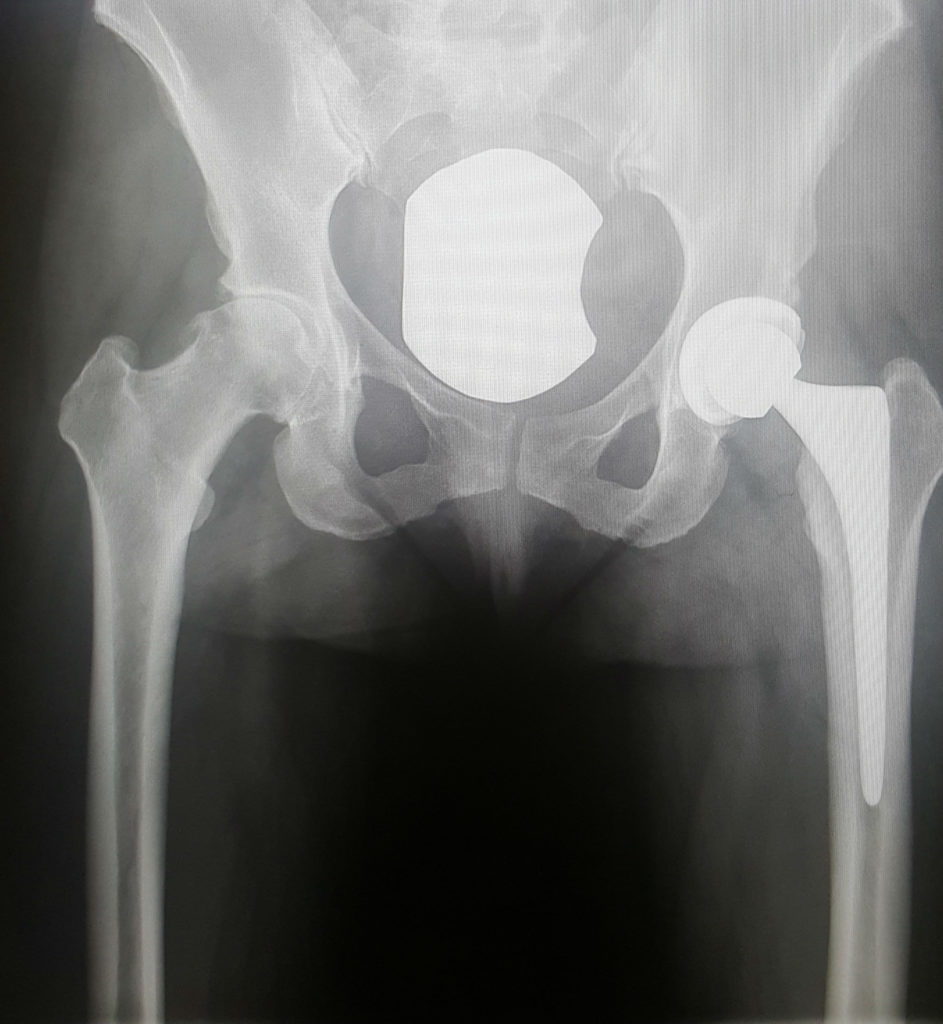

When I first came to HSS I was in complete denial that I was in need of a total hip replacement at the age of 42. I fought it tooth and nail but my quality of life had deteriorated to the point of chronic pain for three straight years. I had been seeing an orthopedist elsewhere and came to HSS for a second opinion. When I met Dr. Nawabi, I immediately felt that I was in very good hands. He was not pushy or knife happy, he listened to my many (many) questions and stayed until every last question was answered. When I left his office, I felt as though I had been very well informed and educated on my condition and my options. I have never been more terrified by anything in my entire life, but Dr. Nawabi made me feel very confident in my decision to have a total hip replacement. Had I known then the relief I would get almost instantaneously, I never would have waited as long as I had. Dr. Nawabi made such a difference in my life and knowing that I will eventually need to have my other hip replaced as well, there is a calmness now in knowing that I will be cared for by the best of the best.